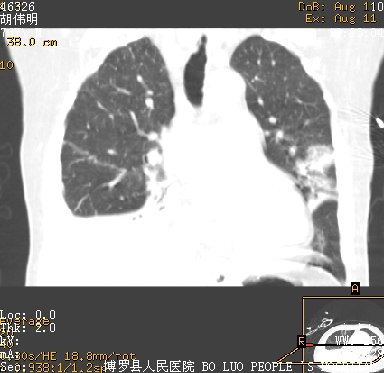

icu病人,几天都没明确诊断。m,76y,咳嗽、咳痰1周,伴气促,右胸痛入院,pe:t38.3c p135 r25 bp135/85。双肺可闻及大量湿罗音,心、腹未见明显异常。诊断:1心衰?2肺部感染?3冠心病?

9号平片

11号ct

双肺感染性病变,下叶膨胀不全,胸水,左室大。

1)两肺感染性病变(右肺下叶肺脓肿可能)。2)双侧胸腔积液,以右侧为甚。

ards,肺感染性病变,右下叶实变,双侧胸腔积液,右侧为著,叶间胸膜积液,右上肺陈旧性tb纤维灶,左室大。

考虑双肺感染、右肺下叶膨胀不全伴双侧胸腔积液。